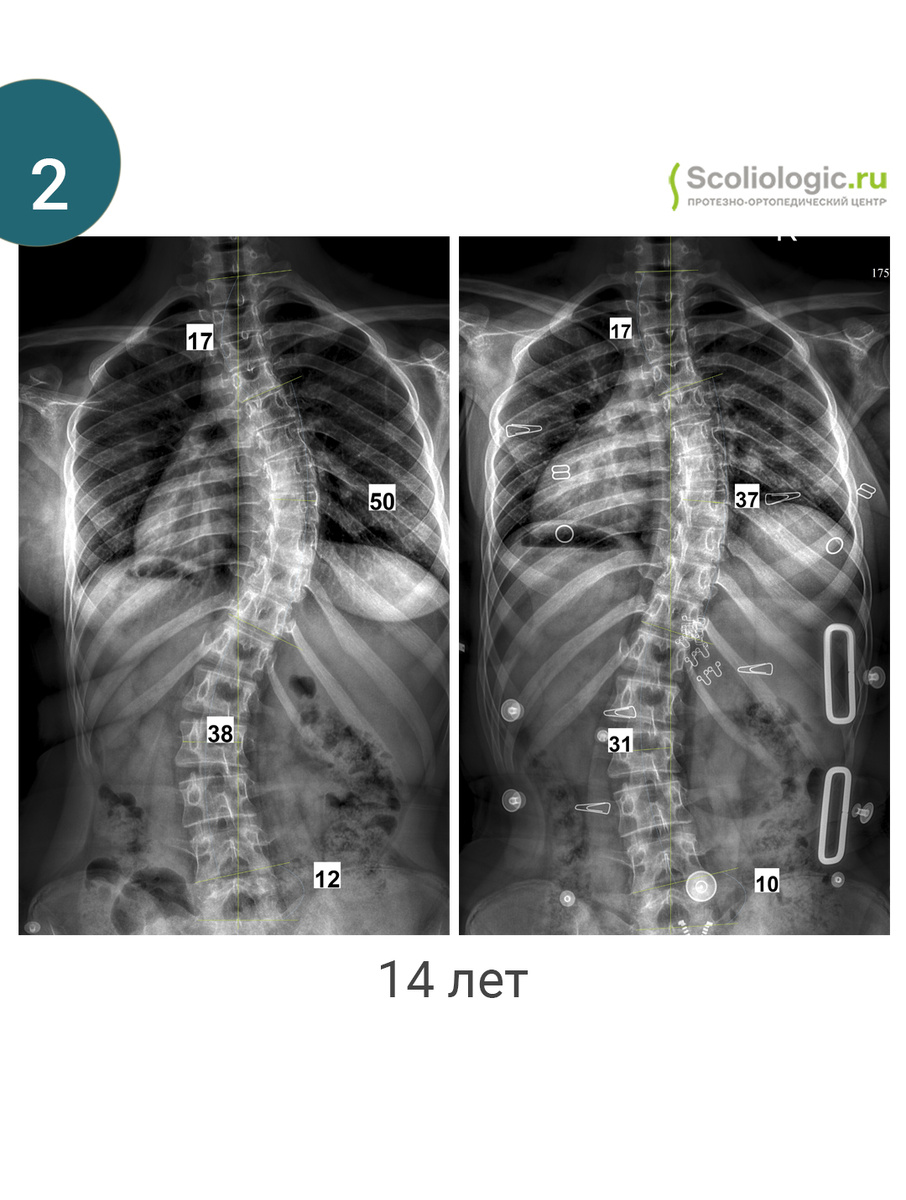

На фото представлены пациенты одного дня и их первые результаты в корсете.

Да, в большинстве случаев коррекция составляет от 25 до 50 % (хотя, это только математика). Но есть и другие случаи.

Фото 6. 35-47-27 градусов. 14 лет. Задача: уйти от операции и улучшить внешний вид. Коррекция грудной дуги в корсете небольшая. В этом конкретном случае дуга высоко, на нее достаточно сложно повлиять. Пациентке уже 14 лет. Но если «передавим», то может измениться верхнегрудная дуга. Тут важен баланс давления на каждую дугу, а также внимание на деротационный момент.